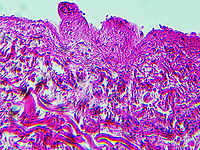

This slide is a skin biopsy from a person infected with Rickettsia rickettsii (the causative agent of Rocky Mountain Spotted Fever). It shows necrosis, vasculitis, and inflammation.